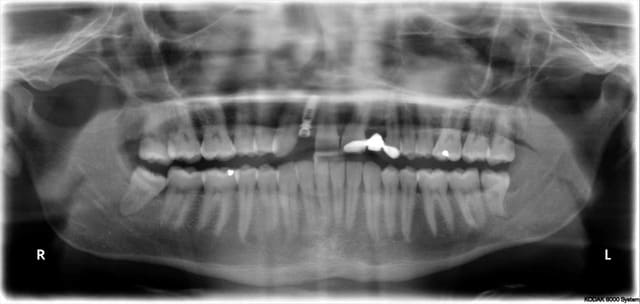

trop tard pour le guide je viens de poser l'implant

mais ton idée est très bonne Patrick, on va réussir à faire un guide fiable et pas cher pour poser ce genre de cas

bien sur à main levé c'est faisable!

utilisation de la clé de clio pour le centrage M-D

pano 1 oups!

pano 2 leger déplacement en mésial de la partie apicale de l'implant

c'est un 3.3x12